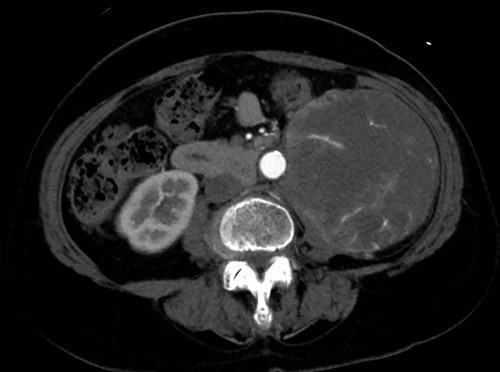

A 76-year-old woman with a giant retroperitoneal tumor was scheduled for surgical resection (Fig. 1). However, preoperative examination revealed severe aortic valve stenosis (AS); therefore, the patient first underwent minimally invasive aortic valve replacement (MICS-AVR) for severe AS. In this operation, we approached the surgical site through the right third intercostal space, and cardiopulmonary bypass was established with right femoral arterial and venous cannulation. PERCEVAL (Livanova, London, UK), a sutureless valve, was used as the artificial valve. Five days post-operatively, she complained of back pain, and a computed tomography (CT) scan revealed bleeding in the tumor and tumor growth. There were no findings of aortic dissection. A peripheral branch of the left third lumbar artery seemed to be the bleeding site; thus, lumbar artery transcatheter artery embolism (TAE) was performed. Although the bleeding stopped, early surgery was considered to be appropriate for the tumor. Therefore, retroperitoneal tumor resection and left nephrectomy were performed on the 12th post-operative day. Four days after tumor resection, the patient suddenly experienced persistent back pain again. CT revealed a Type B AAD. The aorta was dissected from the distal part of the left subclavian artery (LSA) to the level of the right renal artery, and an ulcer-like projection (ULP) was observed at the distal arch (Fig. 2). Although conservative treatment was started immediately, her back pain persisted and follow-up CT revealed slight growth of the ULP. Thus, we decided to perform thoracic endovascular aortic repair (TEVAR) using Valiant (Medtronic, Minneapolis, USA). Before the TEVAR procedure, we performed extra-anatomical bypass from the left common carotid artery to the LSA using PROPATEN (Gore, USA). The Valiant was deployed from Zone2 to just above the celiac artery (Fig. 3). The post-operative course was uneventful, and the patient was discharged without any complications. One year after discharge, CT showed that the aorta was remodeled almost as before (Fig. 4).